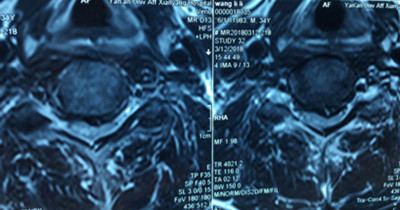

患者王先生,34歲,兩個月來自覺行走時雙下肢無力,伴踩棉花感,休息后癥狀無明顯緩解,雙手指麻木,呈加重趨勢。一月前就診于骨一科。確診為頸椎?。顾栊停?。病變部位位于頸5-6平面。

圖片二:

因患者年齡較輕,雙下肢無力癥狀明顯,病變區(qū)脊髓信號改變,保守治療病情會繼續(xù)發(fā)展,后期脊髓神經(jīng)變性,壓迫癥狀加重,嚴(yán)重影響肢體功能,必須盡早手術(shù)。骨一科主任楊志奎帶領(lǐng)曹熙、田濤、張凱迪醫(yī)師為其實(shí)施了頸椎前路頸5椎體次全切、椎管減壓植骨融合內(nèi)固定術(shù)。手術(shù)歷時3小時順利完成。術(shù)后第二天,患者雙手指麻木癥狀明顯緩解,四肢關(guān)節(jié)活動均正常。第三天配帶頸托保護(hù)下床活動鍛煉,雙下肢無力癥狀明顯減輕。患者現(xiàn)已康復(fù)出院。